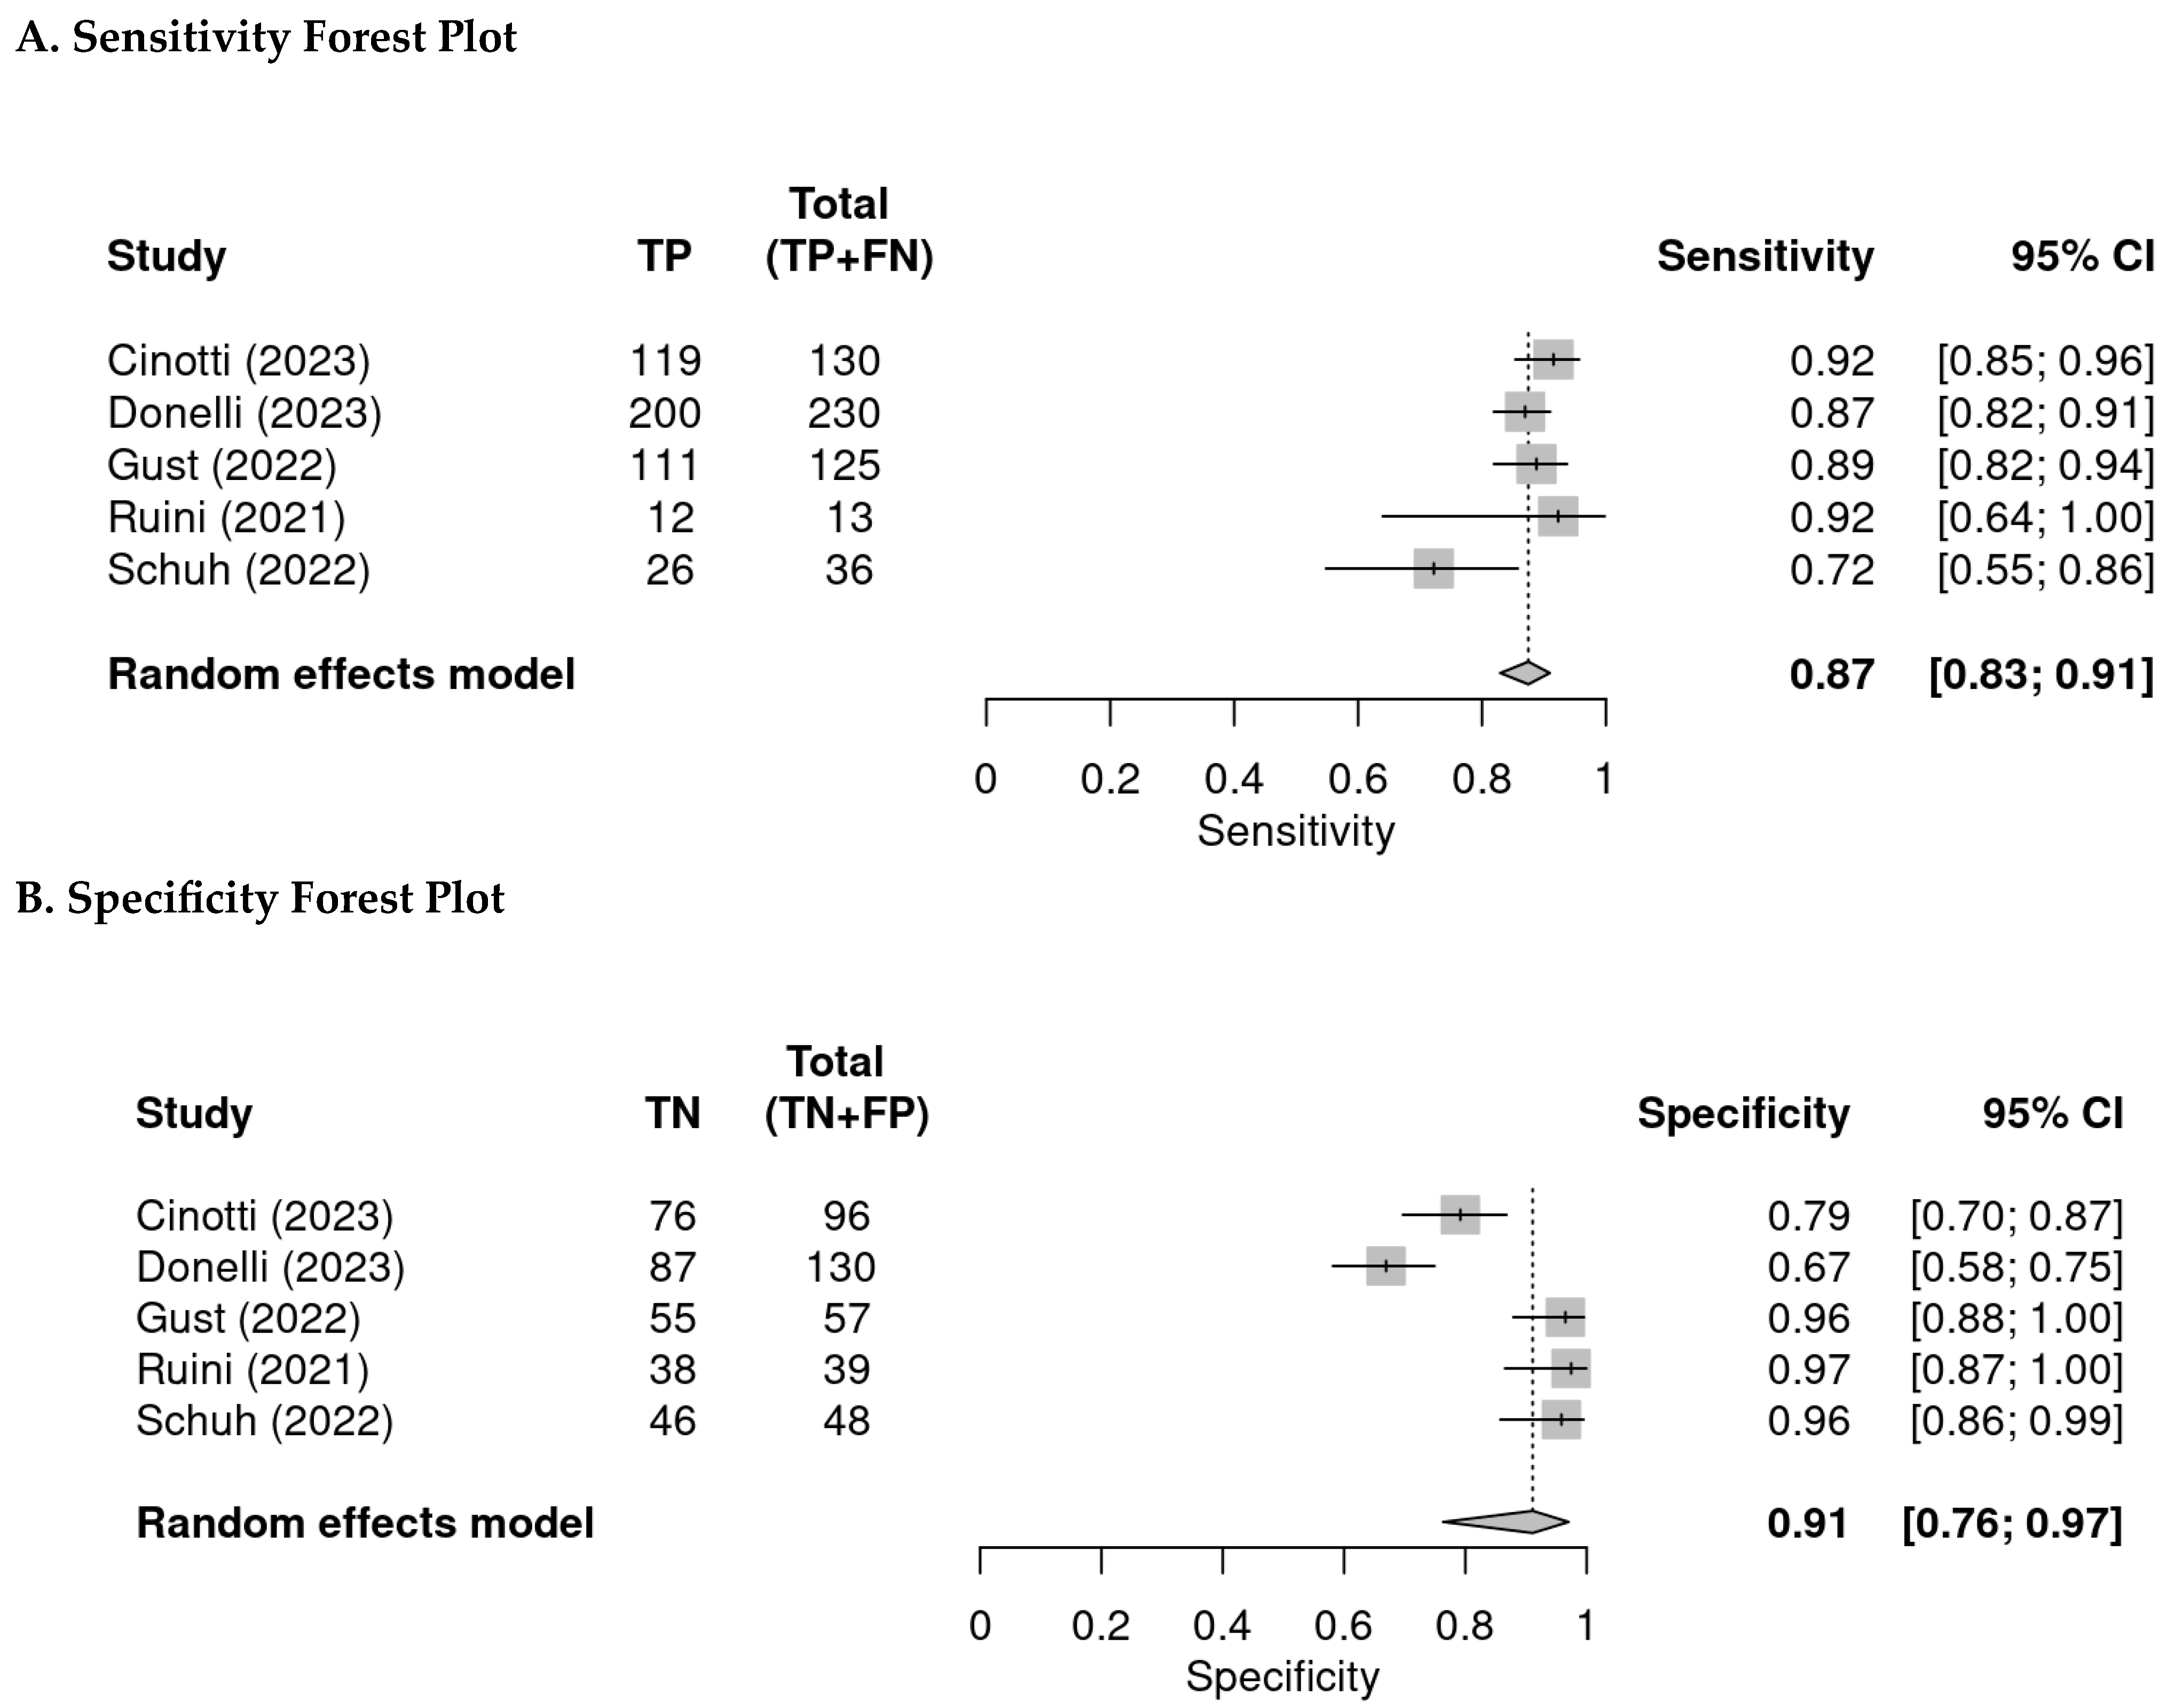

2.4. Statistical Analysis

3.3. Per-Lesion Analysis